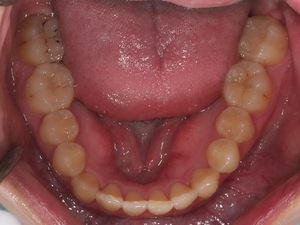

ガタガタとした歯並びや八重歯(叢生)CASE63